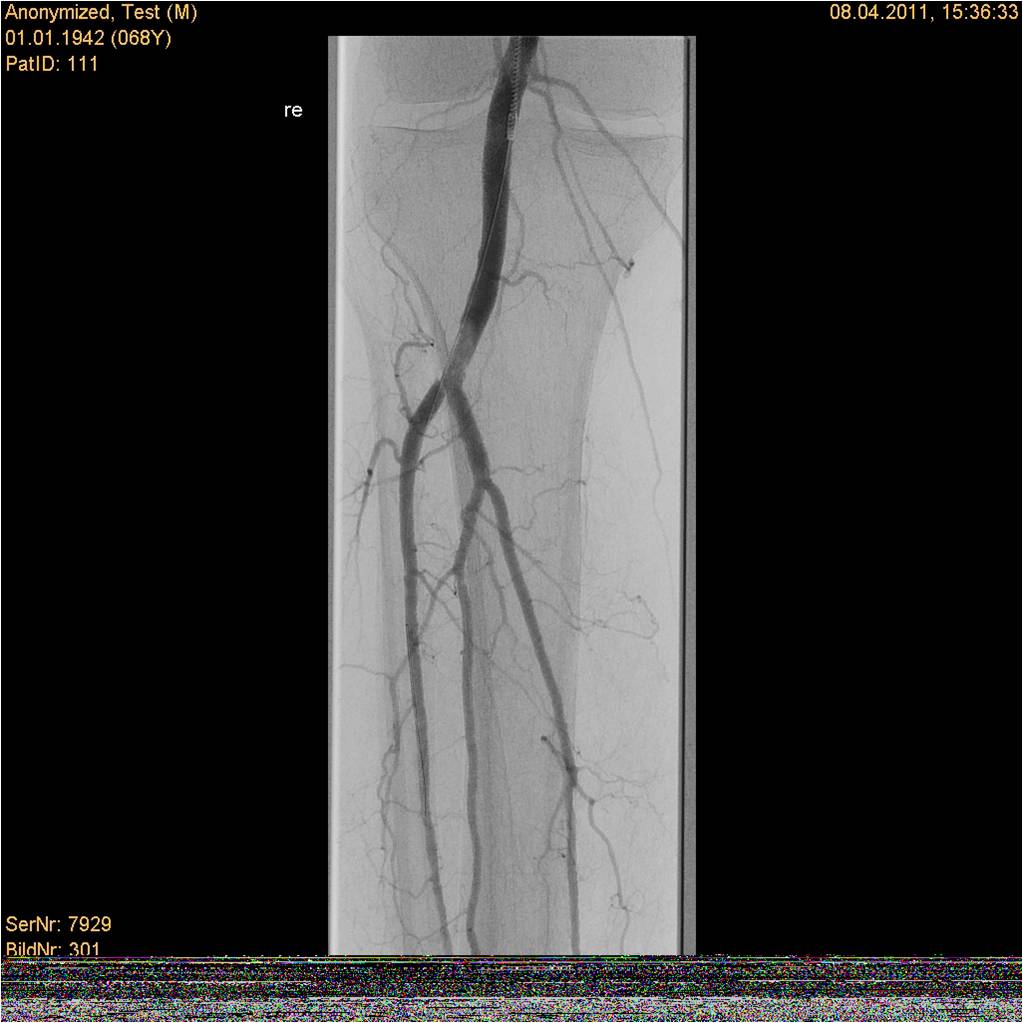

Rotarex®S导管和Straub医疗动力系统配合使用,用于除心肺、冠状动脉和脑循环之外的血管内新鲜、亚急性和慢性阻塞中的血栓、血栓栓塞物和动脉粥样硬化物质的经皮腔内切除。可应用于由动脉粥样硬化、血栓合并栓子、单纯血栓形成所致自体动脉、支架内、旁路血管及透析造瘘血管内的急慢性血栓。

Rotarex®S腔内旋吸导管和Aspirex®S血栓抽吸导管已成为国际上治疗动静脉闭塞性疾病的重要治疗方法之一。随着CFDA证书的获批,中国的外周血管介入专家可使用该腔内导管系统为其病人治疗各种不同的血管闭塞性疾病。自2008年Rotarex®S腔内旋吸导管和Aspirex®S血栓抽吸导管在瑞士上市以来,Straub血栓抽吸术已在国外得到广泛应用。经临床验证安全、可靠、高效。